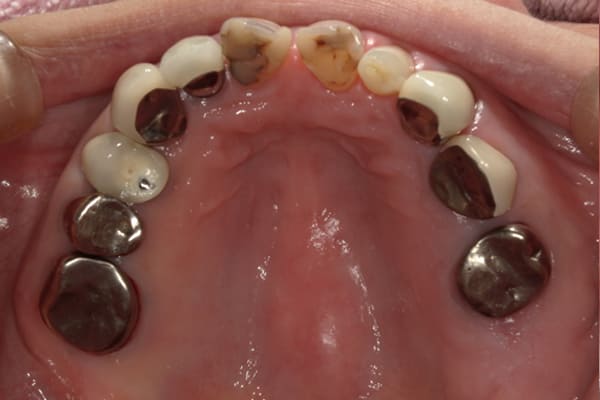

上顎治療前

-

上顎治療後

根のみの7本は虫歯にもなっており歯肉は腫れあがっています。

残りの歯もレントゲンで重度の歯周炎によりぐらぐらな状態でした。

治療前の入れ歯の奥歯は、治療後の義歯と比較しても分かるように、歯が削れ平らになった状態です。

これにより奥歯のかみ合わせは低くなり、前歯のみが強くあたり、かみ合わせにより上の前歯大きな負担がかかっていたことにより、上の前歯が折れたことが考えられます。